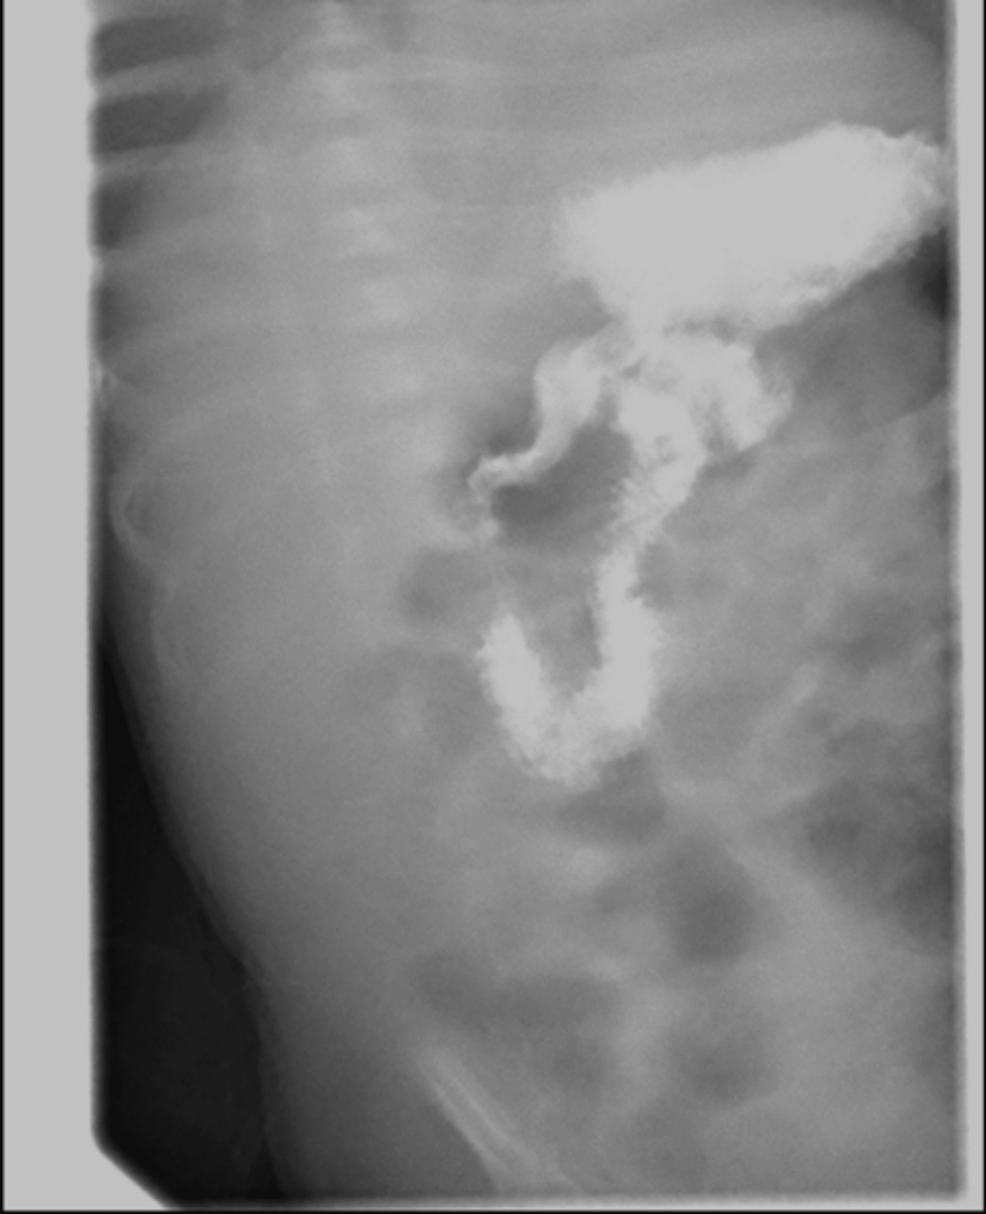

Congenital Hypertrophic pyloric stenosis (CHPS) Creative Med Doses

From creativemeddoses.com